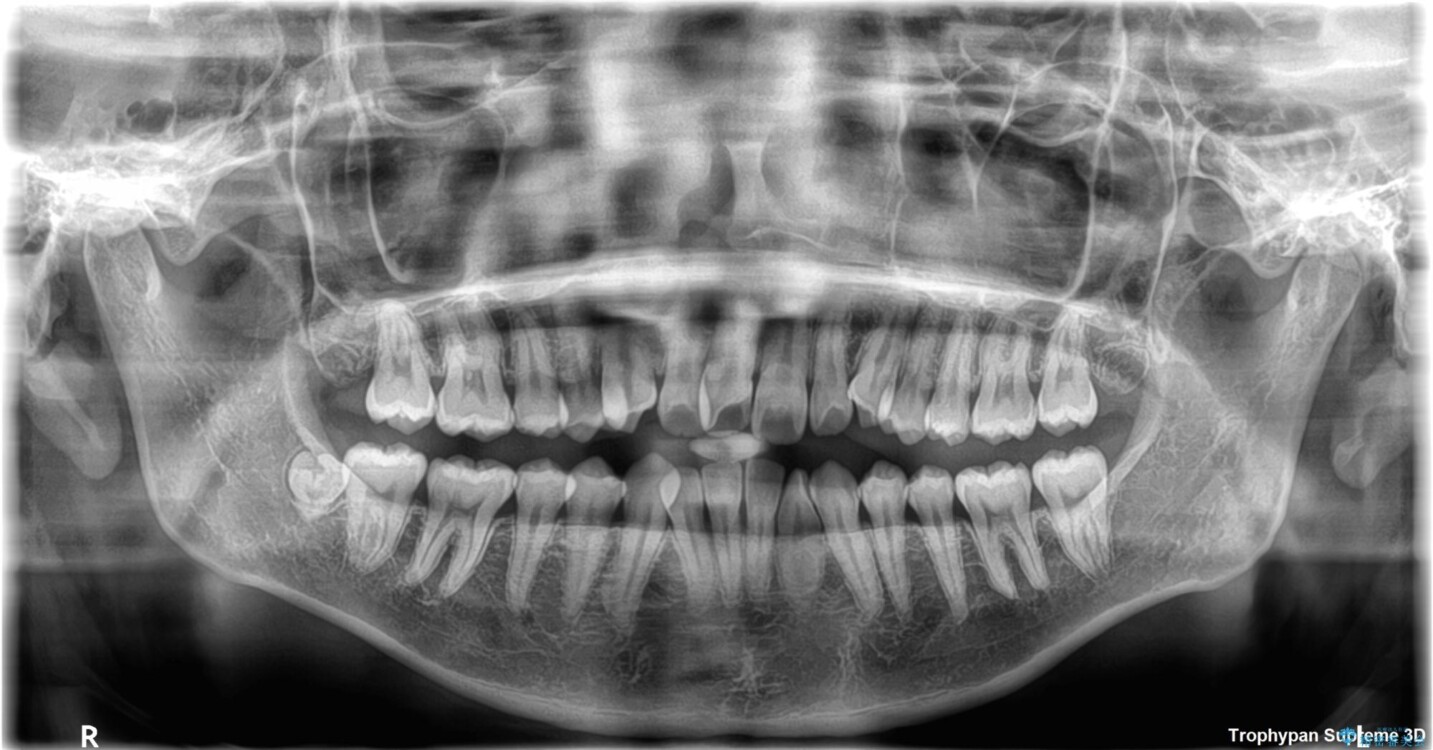

「前歯のデコボコ(叢生)をきれいに整えたい」とのことでご来院されました。

治療計画

マウスピース矯正も検討されていましたが、「装着時間の自己管理が難しそう」「なるべく早く治療を終えたい」とのご希望から、ワイヤー矯正を選択されました。

目立ちにくさと費用のバランスを考慮し、プラスチックブラケット+メタルワイヤーを採用。日常生活でも装置の存在感を気にせずお過ごしいただけます。

患者様の協力もあり、およそ1年間で治療を完了。スムーズな歯の移動を実現しました。

上下の正中(真ん中のライン)もずれることなく、バランスの取れた美しい歯並びに。笑顔に自信を持てる仕上がりとなりました。

・症状により、抜歯が必要な場合があります。